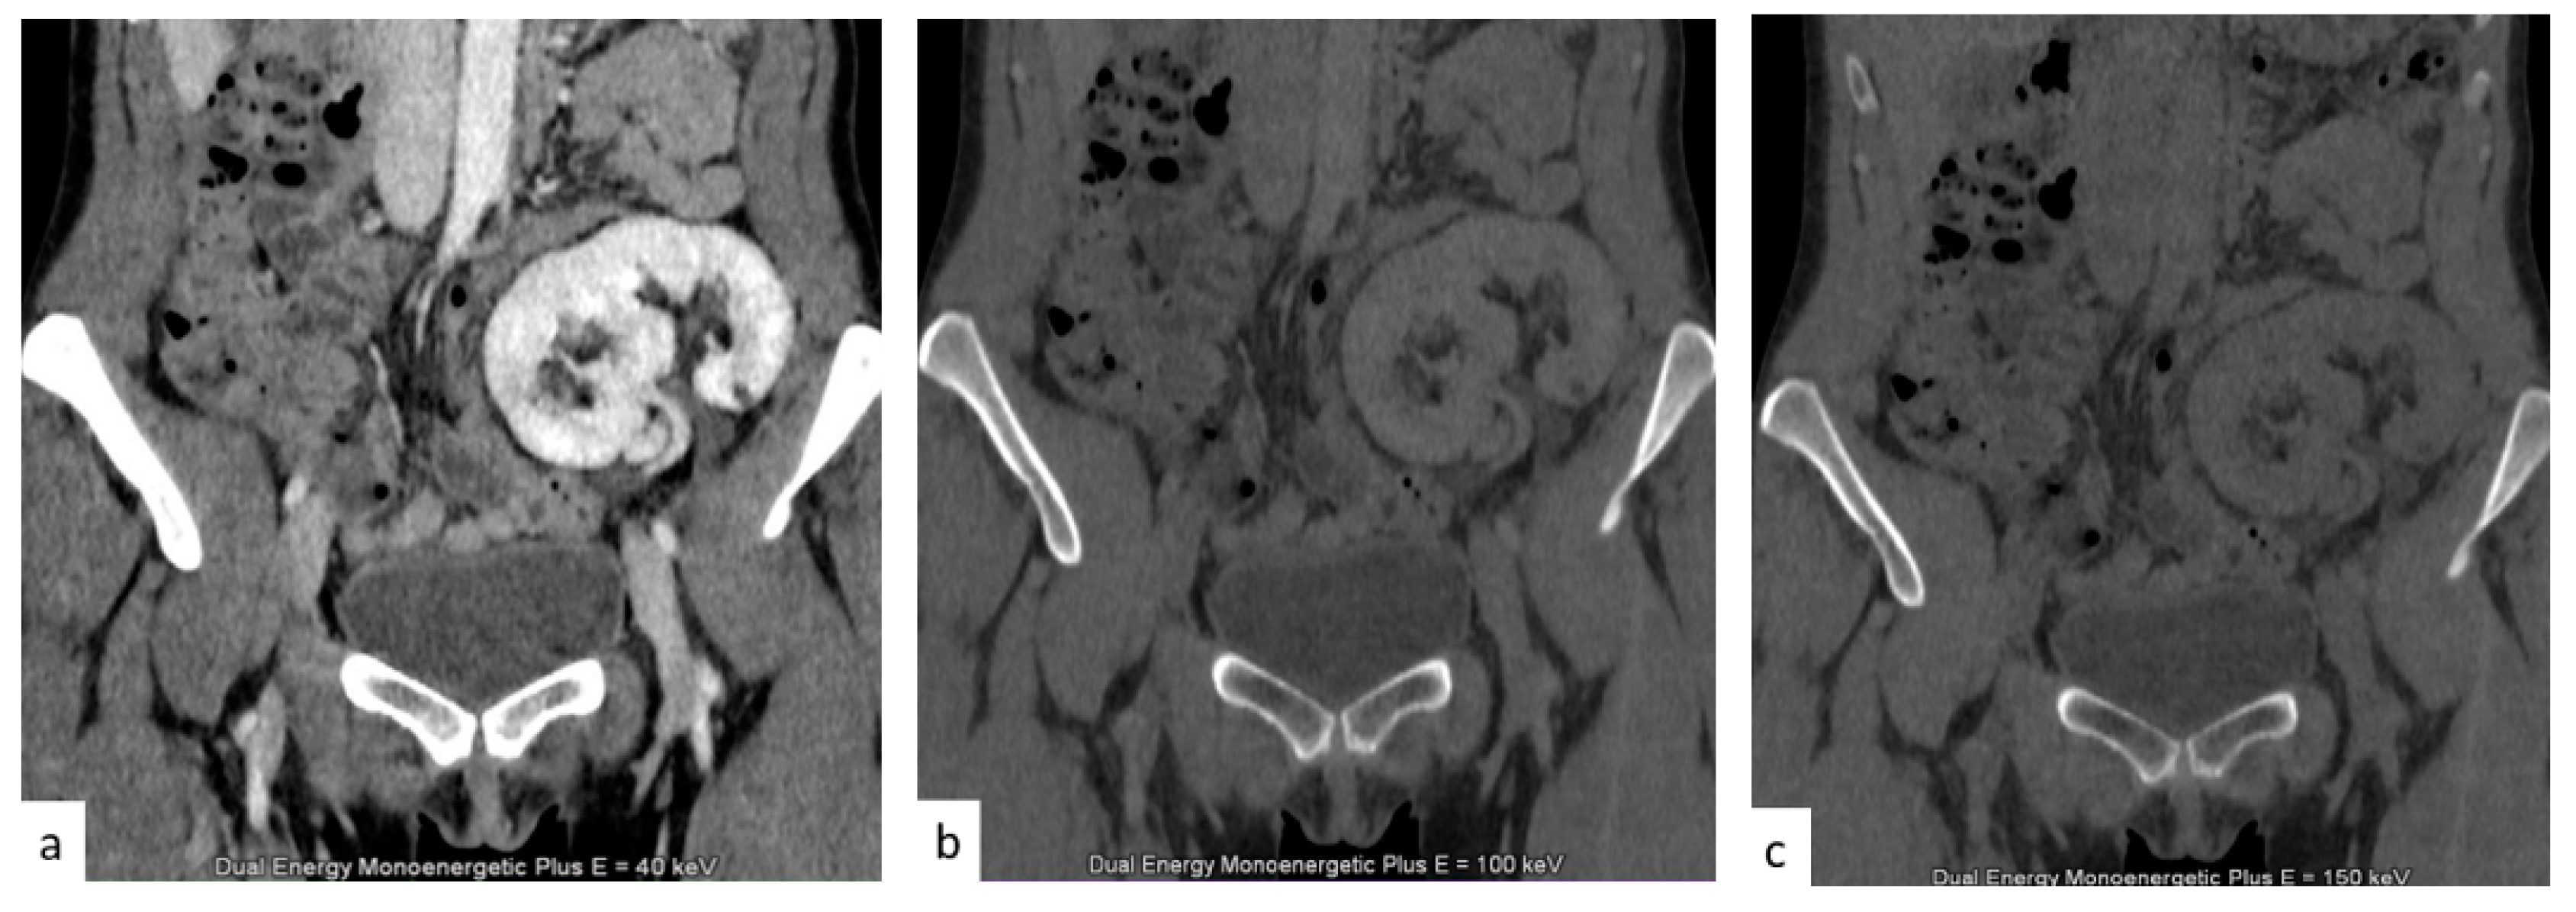

4.3. DECT Contrast Media Reduction

DECT also allows the reduction of the contrast medium dose [63] by using low-energy monoenergetic beams. This is especially useful in patients with a pre-existing renal impairment and a higher risk of contrast-induced nephropathy, as well as elderly patients and patients undergoing routine follow-up [64]. DECT allows synthetic image reconstruction at monochromatic energy levels closer to iodine’s K-edge, where iodine has a substantially higher attenuation than in traditional single-energy acquisition at 120 kVp; this higher attenuation allows a 30% [65,66] reduction in the administered iodine dose for DECT urography when compared to the standard single-energy technique, without compromising attenuation and image quality [67]. Mean DECT attenuation at 50 keV was demonstrated to result in renal vascular and urinary tract attenuation at similar or higher levels than those obtained with the 120 kVp standard acquisition method, with a similar image quality [66].